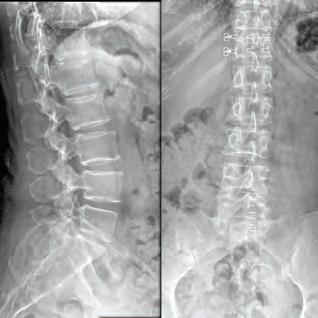

Avoiding and Manipulating a Dowager’s Hump

Dowager’s hump, neck hump, text hump, hunchback, or round back area all names for the same condition. There are a few different labels for the excessive bend in your spine. There are a number of difference causes of dowager’s humps, the most prevalent of which are postural, congenital, and Scheuermann’s.

The term “dowager’s hump” refers to the slightly rounded hump that can sometimes be seen at the base of an elderly woman’s neck, however the condition can occur in people of either sex.

What is a dowager’s hump?

Considered a spinal condition, the chronic forward-leaning posture that is all too frequent in our world of computer screens and other devices is the cause of this ailment, is named “kyphosis” in the medical community. If you have a propensity of slouching all the time, it’s possible that your top vertebrae will develop an unnatural bend over time. Your spine has natural curves to it, which helps you stand straight and supports your posture, but kyphosis can affect your posture and make standing a challenge.

What causes it?

Poor posture is the leading contributor to the development of a dowager’s hump. Because of this, a dowager’s hump most commonly appears between the ages of 40 and 60. Ths forward-leaning and humped posture is frequently the result of tight muscles in the chest and neck, as well as weak muscles in the upper back and neck. Other possible causes include:

• Osteoporosis. A compression fracture causes an increased forward curve. Ths causes your upper back to curve more, which forces you to lift our neck into more extension to be able to see forward. It’s those two factors that cause the bump in the upper back. Women are more likely to develop a Dowager’s hump, as hormone changes during menopause can increase their risk of osteoporosis.Degenerative changes in your spine. Ths is a slow, progressive loss of the normal structure and function of your spine. Degenerative changes range from mild to severe and most often occur as a result of the normal aging process. Arthritis, tumors and infections can also cause these changes.

The hump at the base of your neck may be caused by osteoporosis or poor posture.

• Underlying bony or ligamentous pathologies. Spinal infections, fractures, tumors, calcifiations of spinal ligaments and other bony or ligamentous pathologies can also change the shape of your spine.